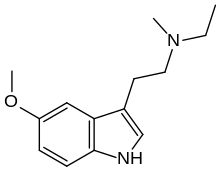

| 5-MeO-MET | artificial | 5-OCH3 | CH2CH3 | CH3 | 5-methoxy-N-Methyl-N-ethyltryptamine | 16977-53-0 |